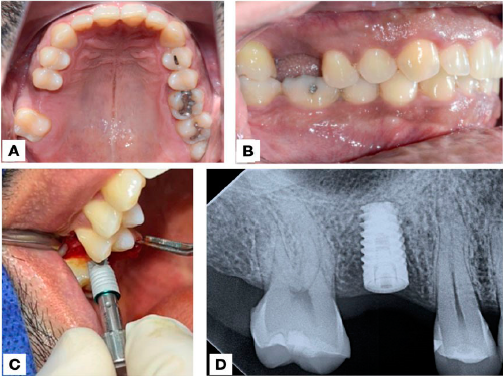

En la valoración clínica, fotográfica y radiográfica (Figura 1. A-B), se encontraron las condiciones adecuadas para la colocación de un implante dental en la zona del diente 16, tales como: altura y anchura óseas suficientes, más de 7 mm de espacio interoclusal para la prótesis fija implantosoportada, y suficiente encía queratinizada sin defectos mucogingivales en la zona a tratar. A continuación, se hizo la planeación tomográfica mediante un equipo de cbct (Orthopantomograph® OP300, Instrumentarium Dental, Tuusula, Finland) y el software Blue Sky Plan® versión 4.0 (Blue Sky Bio, LLC, Libertyville, Estados Unidos), elaboró un mapeo tridimensional de la zona. Se observó un hueso tipo 3 en la zona edéntula y un proceso regular y definido, sin alteraciones y con las dimensiones adecuadas para la colocación del implante dental.

Figura 1 Fotografías iniciales. A. Oclusal pre-operatoria del maxilar. B. Lateral izquierda (pre-operatoria). C. Colocación de implante en zona del diente 16. D. Radiografía dentoalveolar digital post-operatoria.

Se procedió con la colocación del implante, Ø 5.00, longitud 10 mm (Seven XD, MIS® Implants Technologies Ltd., Northern District, Israel). Previa asepsia y antisepsia con Clorhexidina 0.12% intraoral por 1 minuto, se anestesió localmente con dos cartuchos de lidocaína HCI-epinefrina (2%-1:100,000) (FD®, Laboratorios Zeyco®, S.A. de C.V., Zapopan, México). La técnica anestésica consistió en un bloqueo de nervio alveolar maxilar posterior, infiltración en la mucosa de la cara vestibular del área del primer molar maxilar derecho y el bloqueo del nervio palatino mayor. Posteriormente, se realizó colgajo de espesura total con incisión supracrestal, de la cara mesial del segundo molar maxilar derecho a la cara distal del segundo premolar maxilar derecho, liberando el surco gingival en ambos dientes (Figura 1. C).

El sitio implantario fue hecho de acuerdo con las guías del fabricante, y el implante fue atornillado a 25 Ncm de torque inicial. A continuación, se situó el tornillo tapa, provisto en el kit del implante, y se suturó con tres puntos simples interrumpidos con sutura de Nylon calibre 3-0 (Atramat® Nylon Monofilament, Internacional Farmacéutica, S.A. de C.V., Ciudad de México, México). Se tomó una radiografía dentoalveolar digital, en donde se observó una posición adecuada del implante con suficiente hueso alrededor del mismo y una distancia de seguridad hacia el piso del seno maxilar y las raíces de los dientes adyacentes (Figura 1.D).